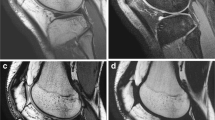

On FS PDw TSE MR imaging, intact cartilage appeared with low to intermediate signal (Fig. 1). High signal intensity of joint fluid and cartilage edema assisted in the visualization of cartilage contour irregularities and internal derangement (Fig. 2, 3, 4). Fifty-eight findings were true-positive, six false-negative (3 grade 1a, 1 grade 1b, 1 grade 2a, 1 grade 2b), two false-positive, and 90 true-negative (Table 1). Sensitivity, specificity, positive predictive value, negative predictive value, and accuracy were 91%, 98%, 96%, 94%, and 95%, respectively. The correlation between arthroscopy and FS PDw TSE for grading and sizing cartilage lesions was significant in all compartments (Tables 2, 3).

MR imaging with FS PDw TSE was highly specific and sensitive for the detection of cartilage lesions and correlated significantly with arthroscopy for grading and sizing in each compartment. Intact cartilage appeared with a low to intermediate signal. FS PDw TSE MR imaging has several advantages. It provides information on cartilage water content and therefore edema assists in the visualization of cartilage subsurface derangement [19]. The arthrographic effect of the joint fluid assists in the visualization of cartilage surface irregularities, which may obviate the need for MR arthrography. Furthermore, static field inhomogeneity is compensated by the refocusing effect of the 180º flip angle [1, 20, 21]. These factors can explain why cartilage derangement is better visible on FS PDw TSE MR imaging. Additionally the technique is well suited for imaging of other joint structures, which allows a sufficient evaluation of the entire joint in one step [6, 18, 22, 23, 24]. Our results compare well with those of Potter et al. [6] who showed, in 88 patients, a sensitivity, specificity, and accuracy of 87%, 94%, and 92%, respectively, for a fat-saturated PDw spin echo sequence . In 27 patients Gagliardi et al. [21] found a sensitivity, specificity, and accuracy of up to 75%, 100%, and 98% respectively, for the detection of patellar cartilage lesions. The lower sensitivity in this study may be explained by the fact that no fat saturation was used. The latter, however, is often included in clinical imaging protocols to expand the dynamic range of MR imaging for subtle cartilage variations, to intensify cartilage signal, and to reduce chemical shift artifacts [1, 14, 16]. Bachmann et al. [4] used a PDw sequence and reported in 50 knees a remarkably lower sensitivity and accuracy of 45% and 64%, respectively, but a comparable specificity of 98%. Recht et al. [14] reported worse results with a sensitivity, specificity, and accuracy of 25%, 95%, and 70%, respectively. The discrepancy between these two studies and those of Potter et al. [6], Gagliardi et al. [21] and the present study may be explained by the use of cadaver knees with MR imaging after freezing, storing, and thawing, which may affect signal intensities [25]. These procedures may cause diffusion effects of articular fluid or intra-cartilaginous edema in addition to post mortem changes. Additionally neither study included fat saturation, which could improve the detectability of cartilage lesions. Furthermore, Gagliardi et al. [21], Bachmann et al. [4], and Recht et al. [14] used either a smaller matrix, resulting in lower spatial resolution, only the transverse imaging plane, or a higher slice thickness in their imaging protocol, which may lower the detection rate of cartilage defects. Disadvantages of the technique can be magic angle artifact, the 2D acquisition principle and a lower contrast between cartilage and subchondral bone, which make it less suitable for cartilage thickness and volume measurements [8, 9, 10].